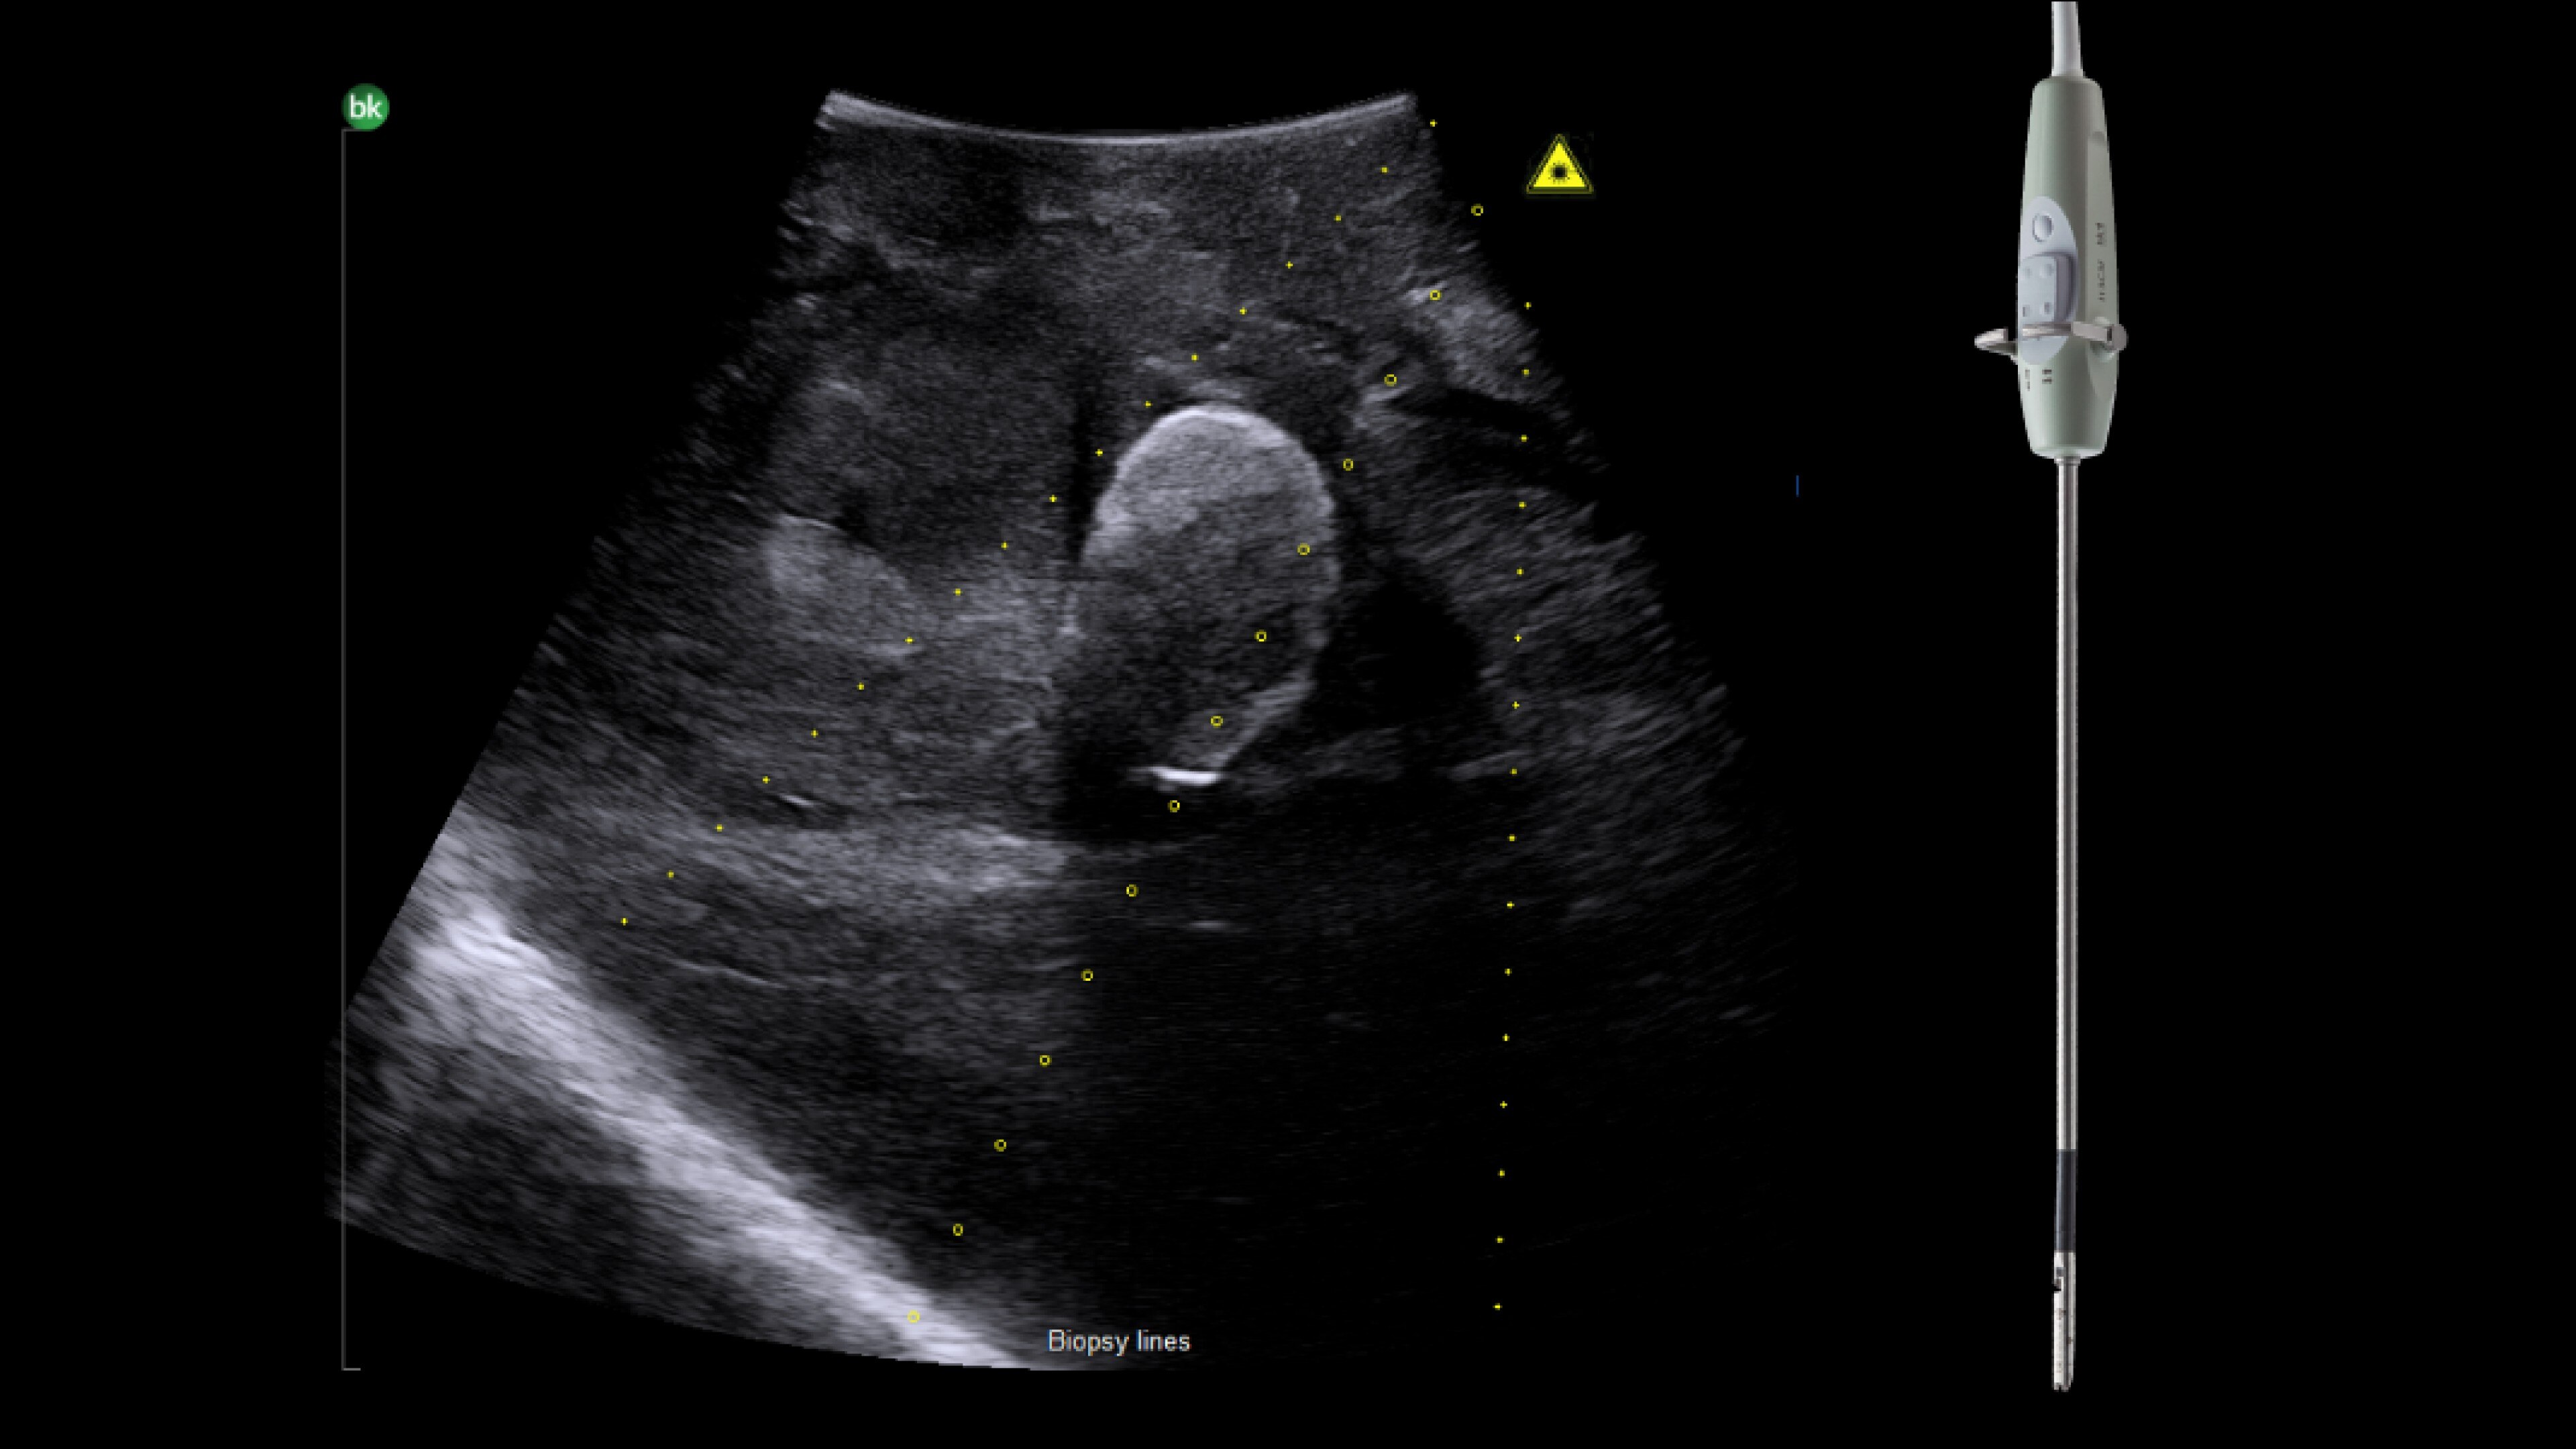

Advanced Laparoscopic Transducer I13C3f*

• Plan and target tumor biopsies and ablations with patented laser technology.

• Achieve preferred insertion angle on up to two needles with proprietary channel design.

*I13C3f has not been licensed by Health Canada.